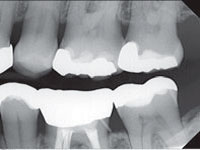

В отличие от рентгенографии при радиовизиографии рентгеновские лучи попадают не на пленку, а на датчик, состоящий из множества детекторов. В результате воздействия ионизирующего излучения в каждом детекторе возникает определенной величины заряд. Компьютер, последовательно опрашивая детекторы, собирает информацию со всей площади датчика и формирует на экране монитора изображение, яркость све¬чения каждой точки (пиксели) которого соответствует величине заряда на детекторе, расположенном в дан¬ном конкретном месте. После того как компьютер про¬ведет опрос детектора, заряд на нем исчезает и датчик подготавливается к следующему экспонированию. Снижена лучевая нагрузка на пациента в 10—20 раз, или на 90—95%, чем при рентгене. Именно во столько раз детекторы современного  радиовизиографа  более чувствительны к рентгеновским лучам, чем обычная пленка.

Снимок можно распечатать на принтере или сохранить в электронной карте пациента для последующих приёмов.

Рентгеновские изображения, полученные на HELIODENT

PLUS, характеризуются высокой детализацией и контрастностью, что позволяет использовать их по широкому ряду показаний.

Рентгенологические методы исследования являются незаменимыми в качестве диагностического инструмента. На сегодняшний день многие врачи используют далеко не все возможности рентгеновского исследования. А между тем это позволяет не только верно планировать лечение, но и достичь стабильных функциональных и эстетических результатов.